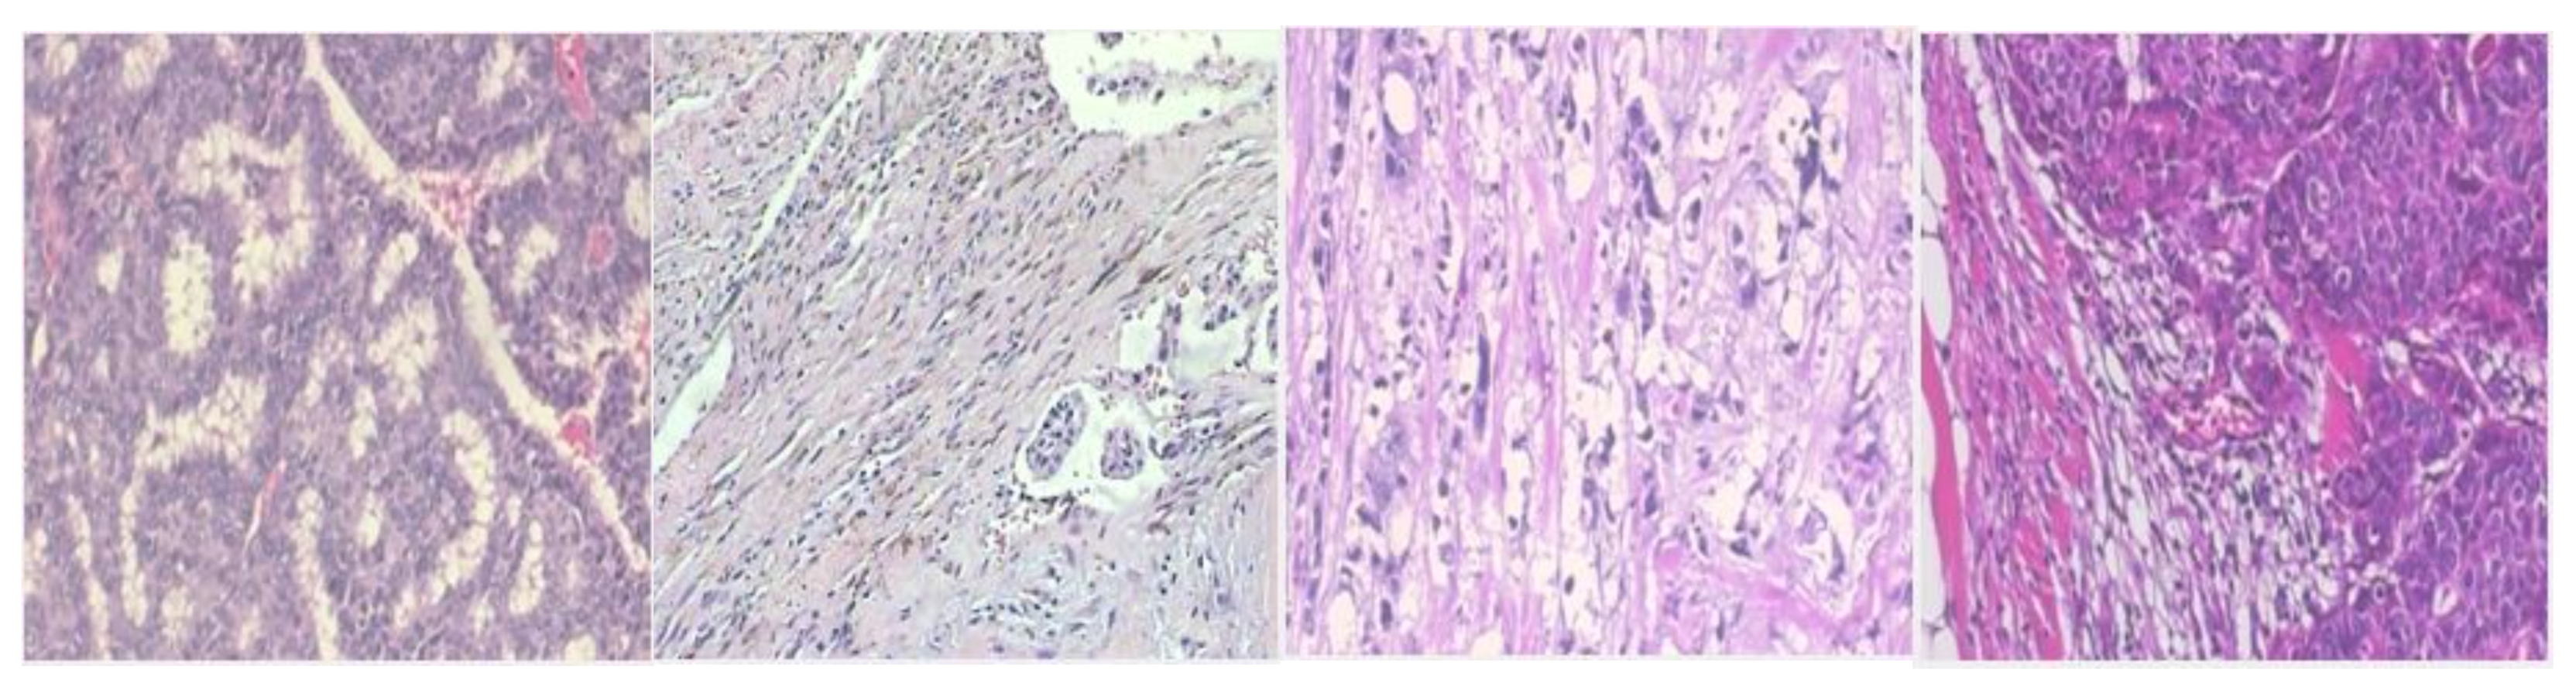

We utilized the BreakHis dataset which is a publicly available open image dataset of hematoxylin-eosin (HE) stained histopathological slides. The histopathological images were obtained in four (4) optical intensification factors, specifically 40×, 100×, 200×, and 400× with an efficacious pixel sizes of 0.49 m, at 0.20 m, at 0.10 m, and at 0.0 m. The images were saved in RGB format in true color space. The pathologist spots a distinctive and appropriate region of interest (ROI) for diagnosis in every patient. The unwanted region, for instance, text clarification or dim edge was eliminated, and the images were edited to a component of 700 × 460 pixels. The distribution of benign and malignant images over various subtypes is shown in Table 2, and the sample images of benign and malignant subtypes are shown in Figure 9 and Figure 10, respectively.

Figure 10. Sample of malignant subtypes: (A) ductal carcinoma; (B) lobular carcinoma; (C) mucinous carcinoma; (D) papillary carcinoma.

Applsci 13 00156 g010